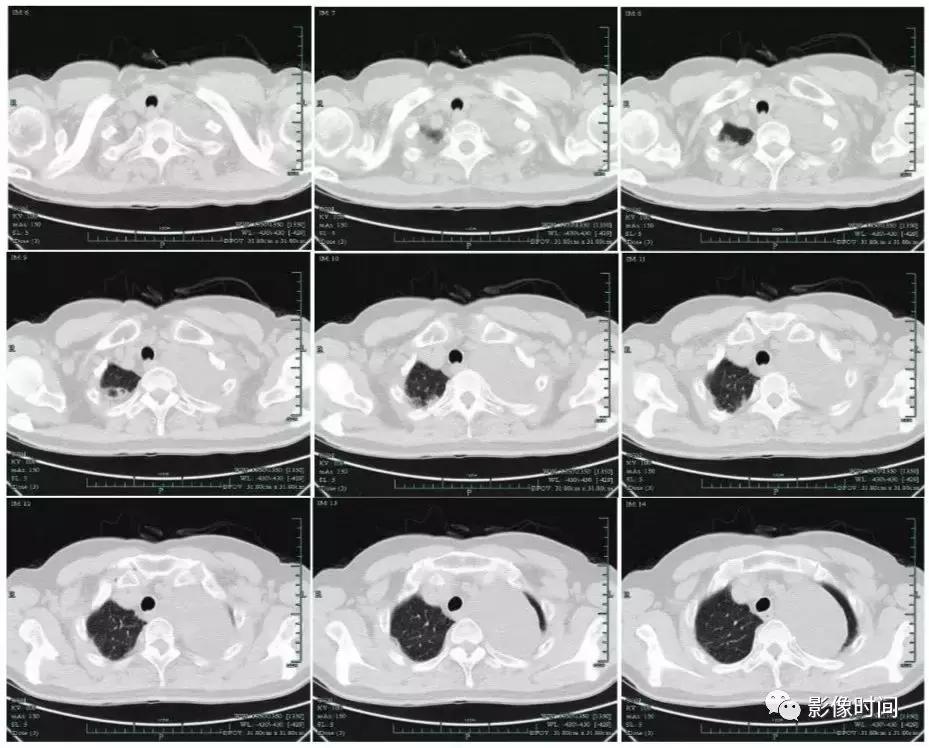

胸部CT平扫+增强

胸部CT平扫+增强提示:左后上纵隔旁可见一约8.4 cm×5.7 cm大小的类圆形低密度影,内密度不均,见片絮状稍高密度影,边界光整,壁薄,增强扫描病灶不均匀强化。

通过以上影像表现可见病变位于后上纵隔旁,良性可能性大,神经源性肿瘤首先考虑。但神经源性肿瘤包括神经鞘瘤、神经纤维瘤(病)、神经节细胞瘤、副神经瘤等。本病例具体属于哪一类肿瘤还需进一步病理鉴别。